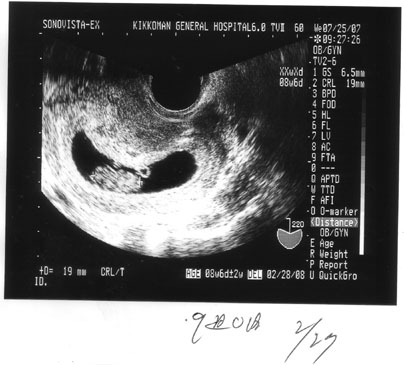

b.jpg9週目に入り、袋が大きくなりましたw

卵から手足がにょきっと生えてます。

頭もあるんですがよくわからないですねえ~

大きさは19㍉